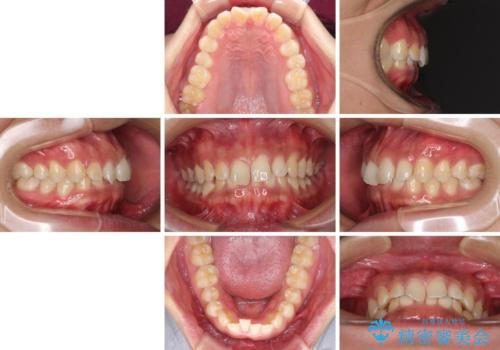

- 前歯のデコボコや隙間と深い咬み合わせ(ディープバイト)を気にして来院された患者様です。

インビザラインによる上下歯列の側方拡大と後方移動、IPR(歯と歯の間を削る)にるスペースの獲得により、デコボコとディープバイトを改善することとしました。

後方移動に際し、上下の親知らずは4本全て抜歯することとしました。

気になっていたデコボコや隙間は改善し、きれいな歯列に整えることができました。

咬合力が非常に強い方であったため、これ以上のディープバイトの改善は困難となりました。